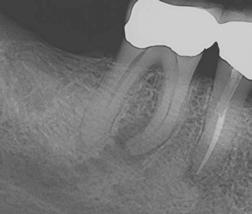

1: 3D print in clear acrylic of maxillary central incisor with mid-root lateral canal and apical canal bifurcation. Note the calcified pulp chamber

accurate prediction because in 2017, after printing resolution got down to 0.016 mm, I was able to print the first extracted tooth replicas in both clear and opaque inks.

Since then, TrueTooth and TrueJaw replicas have been used worldwide, and of course, in my training lab in Santa Barbara. Here are a couple of things I’ve learned in the 8 years since their advent:

Figure

a replica, they will never ledge a human root canal again for the rest of their careers.

4. Clear and opaque replicas are ideal for teaching mental imaging skills. Mental imaging is the most important skill a dentist brings to a root canal party, and while some of us have a natural ability in that regard, most of us need help figuring out how to do that. Training in clear replicas provides a view of exactly what is happening; for instance, when a rotary file is cutting through a curved canal, The best experience is to first do it in a clear replica and see it, then do the same procedure without directly seeing it in an opaque replica. Lots of “aha’s” happen with this teaching method. The results have been amazing (Figures 2-6).